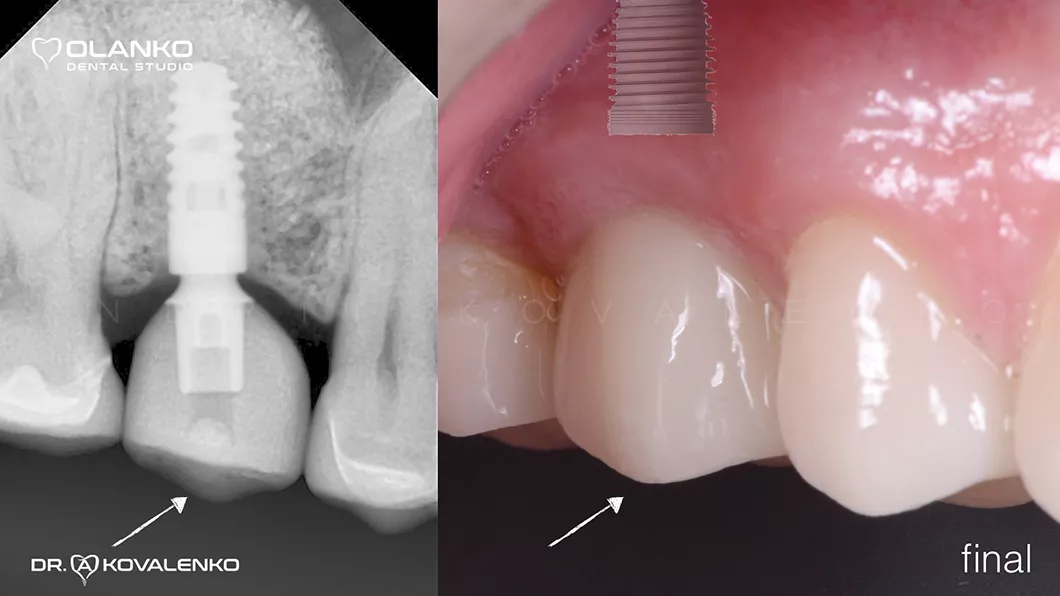

Ситуация после установки коронки ДО/ПОСЛЕ

Ситуация после установки коронки до и после Оланко Бровары Киев